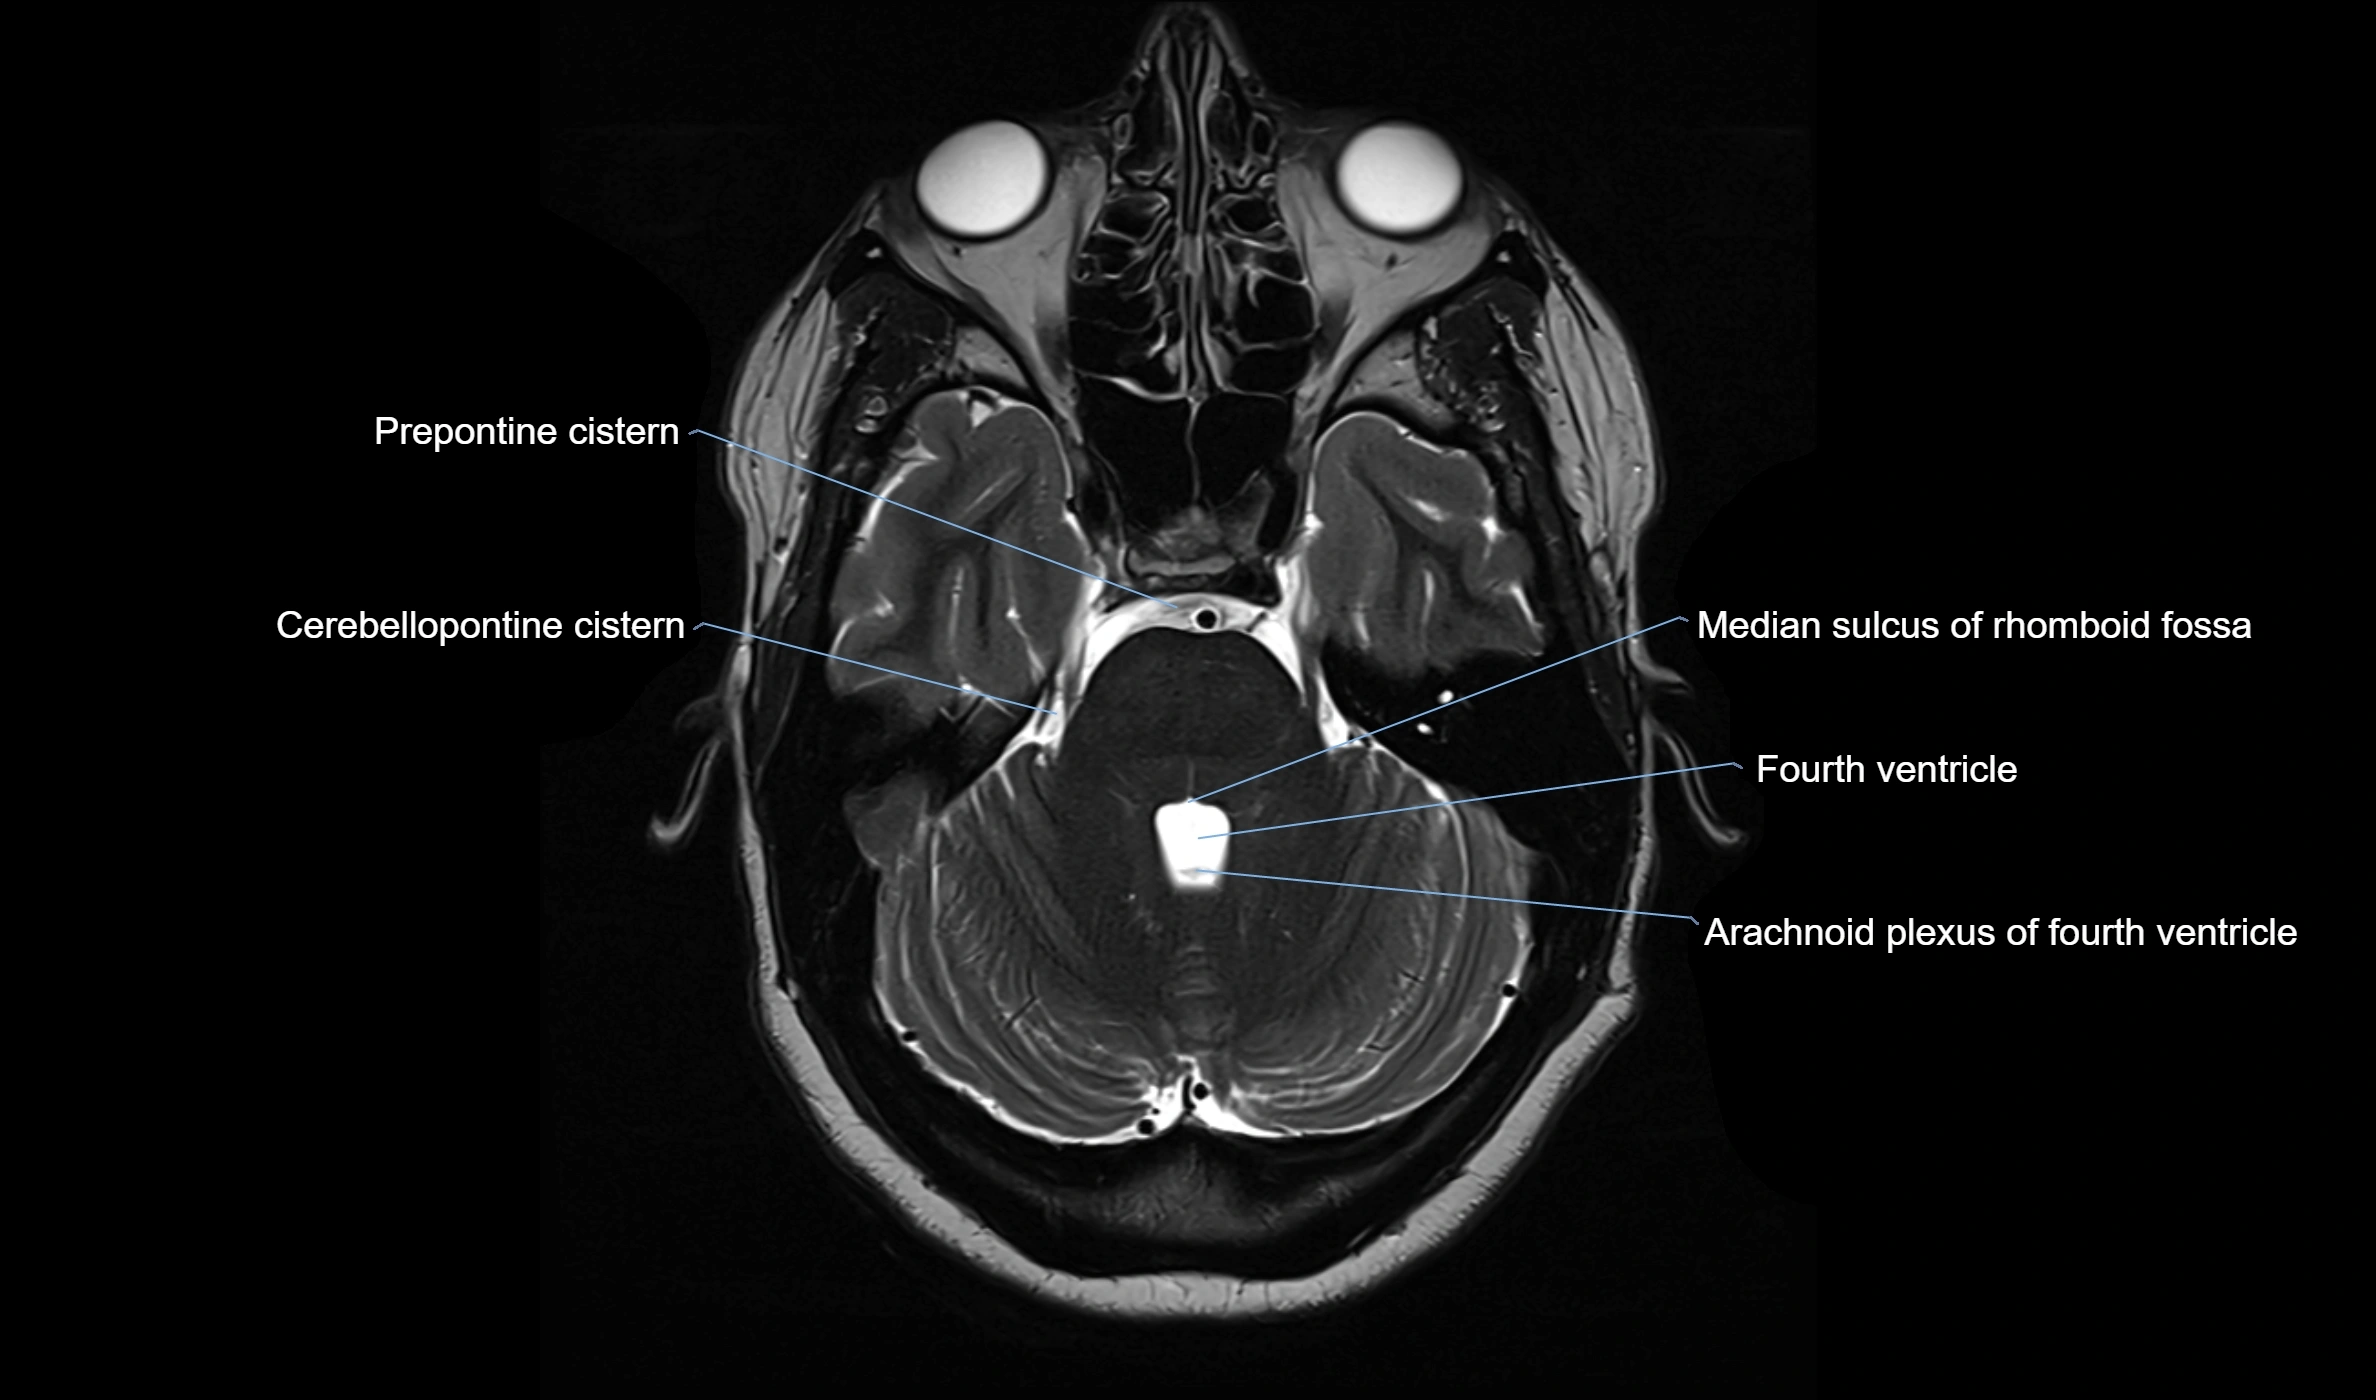

MRI images

image